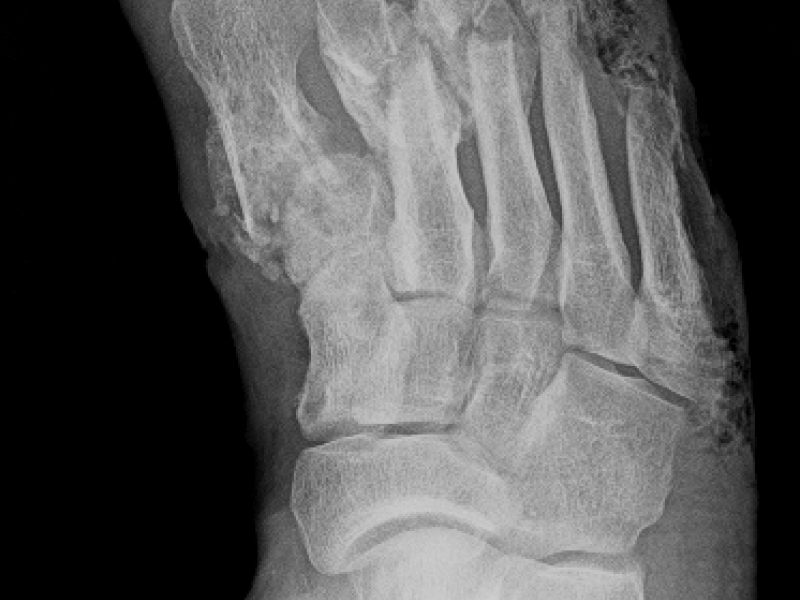

What's the Diagnosis? By Dr. Lauren Murphy

December 13 2017

A 26 yo M presents to the ED with a chief complaint of R